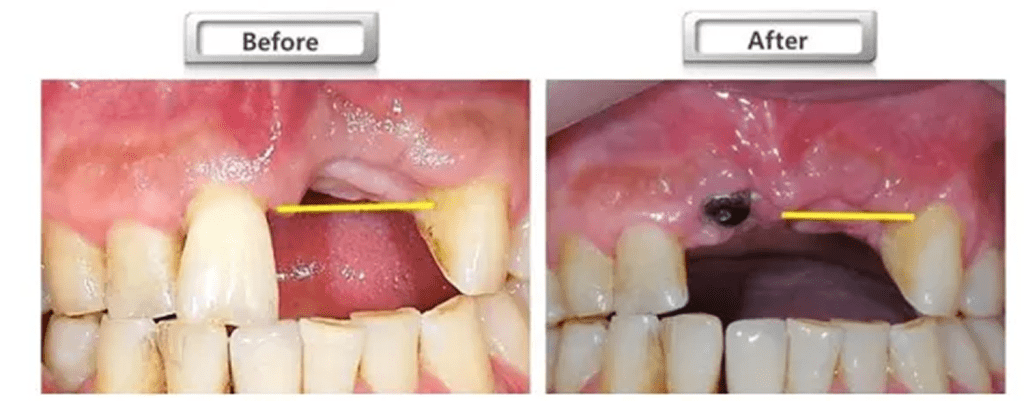

(2) 앞니 임플란트 (태생적으로 얇은 뼈)

앞니는 어금니와 게임이 다릅니다. 앞니 쪽 뼈(특히 바깥쪽)는 원래부터 종잇장처럼 얇은 편입니다. 임플란트가 장기적으로 안정되려면 앞쪽으로 최소 2mm의 뼈 두께가 필요한데, 앞니는 이 조건이 충족되지 않는 경우가 많아요.

뼈이식을 하지 않으면 어떻게 될까요? 시간이 지나면서 얇은 뼈가 흡수되고, 임플란트 나사가 노출될 수 있습니다. 잇몸이 까맣게 비쳐 보이거나 염증이 생기는 문제로 이어져요. 실제로 다른 곳에서 앞니 임플란트 후 몇 년 뒤 이런 문제로 재상담 오시는 분들이 적지 않습니다.

앞니 뼈이식은 건물 공사로 치면 콘크리트만 붓는 게 아니라, 거푸집(차폐막)을 세워서 모양이 무너지지 않게 만든 뒤 굳히는 과정에 가깝습니다. 이 과정을 고수하는 이유는 단순해요. 앞니는 1mm 차이가 티가 나기 때문입니다. 기능뿐 아니라 웃을 때 보이는 잇몸선, 자연스러움, 좌우 대칭이 같이 평가됩니다.